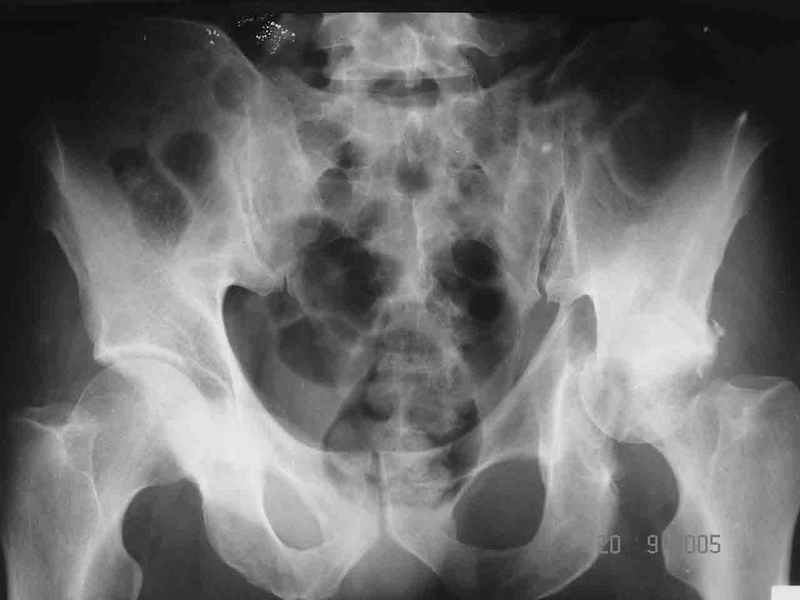

Больной 18 мая 2003 года в автоаварии получил перелом левой вертлужной впадины, вывих бедра. Госпитализирован в один из стационаров области.Вывих вправлен. В последствии бедро вывихивалось еще дважды. На консультацию был представлен снимок от 19.05.03г., больной переведен к нам 3.06.03г. Снимок при поступлении - перелом впадины, задне-верхний вывих бедра. 05.06.2003 г. выполнено открытое вправление вывиха левого бедра и остеосинтез стенки вертлужной впадины двумя винтами. Послеоперационный период без осложнений. Объем движений в левом тазобедренном суставе восстановился полностью. Выписан на амбулаторное лечение в удовлетворительном состоянии с рекомендациями 3 месяца ходить на костылях без нагрузки на оперированную конечность. На контрольных рентгенограммах левого тазобедренного сустава 13.10.2003 г. - признаки консолидации перелома; плотность, форма головки и состояние суставных поверхностей удовлетворительные. Разрешена дозированная осевая нагрузка, на конечность с использованием дополнительной опоры. 19.12.2003 г. больной обратился с жалобами на боли в левом тазобедренном суставе. На рентгенограммах левого тазобедренного сустава 19.12.2003 г., 20.02.04г. - асептичекий некроз головки бедра. 5.04.04г. - эндопротез. Сейчас ходит без трости, не хромает. Особенность эндопротезирования - при удалении винтов прослежена линия перелома заднего края впадины и предложено установить чашку несколько меньшего диаметра, чтобы она была покрыта несломанной частью.

Случай, представленный Вами, совсем не идентичен обсуждаемому. У Вашего пациента был поперечный перелом с переломом заднего края, а в обсуждаемом случае - высокий двухколонный перелом вертлужной впадины.

То есть в представленном Вами случае был перелом заднего типа, в нашем случае центрального. У Вашего больного был застарелый задний вывих, у нашего - перелом шейки. Столь раннее разрушение головки, вероятно, было во многом обусловлено тем, что не была достигнута анатомическая репозиция, головка бедра осталась смещенной кзади, что является частой ошибкой при крупных фрагментах свода.

Необходимость фиксации вертлужной впадины в нашем случае вообще под вопросом, так как конгруэнтность сохранена (вторичная конгруэнтность типична для двухколонных переломов).